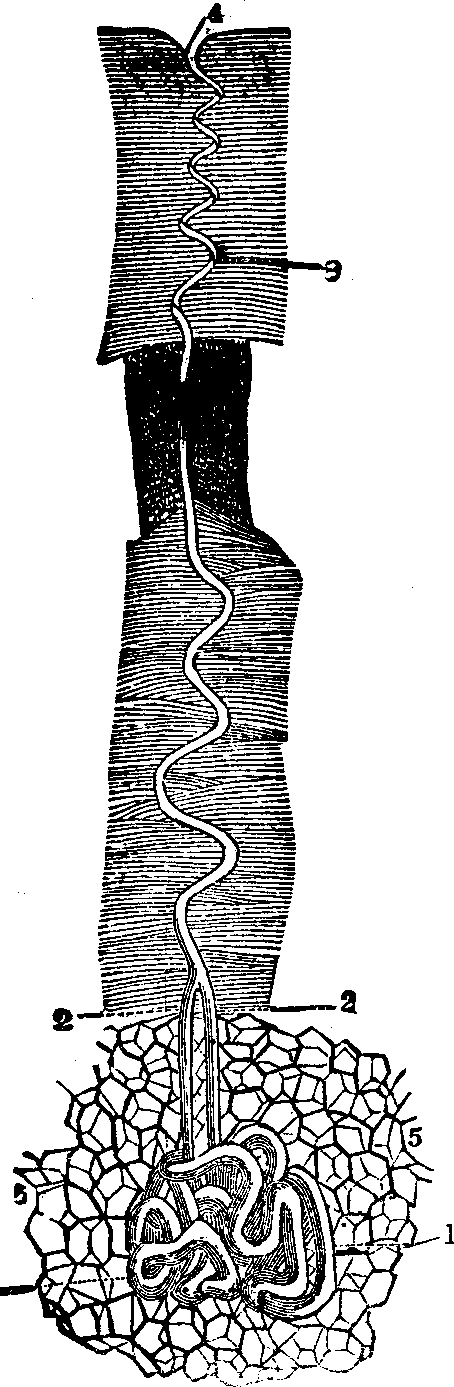

Absorption is the vital function by which nutritive materials are selected and imbibed for the sustenance of the body. Absorption, like all other functional processes, employs agents to effect its purposes, and the villi of the small intestine, with their numberless projecting organs, are specially employed to imbibe fluid substances; this they do with a celerity commensurate to the importance and extent of their duties. They are little vascular prominences of the mucous membrane, arising from the interior surface of the small intestine. Each villus has two sets of vessels. (1.) The blood-vessels, which, by their frequent blending, form a complete net-work beneath the external epithelium; they unite at the base of the villus, forming a minute vein, which is one of the sources of the portal vein. (2.) In the center of the villus is another vessel, with thinner and more transparent walls, which is the commencement of a lacteal.

The Lacteals originate in the walls of the alimentary canal, [pg 49]are very numerous in the small intestine, and, passing between the laminæ of the mesentery, they terminate in the receptaculum chyli, or reservoir for the chyle. The mesentery consists of a double layer of cellular and adipose tissue. It incloses the blood-vessels, lacteals, and nerves of the small intestine, together with its accessory glands. It is joined to the posterior abdominal wall by a narrow root; anteriorly, it is attached to the whole length of the small intestine. The lacteals are known as the absorbents of the intestinal walls, and after digestion is accomplished, are found to contain a white, milky fluid, called chyle. The chyle does not represent the entire product of digestion, but only the fatty substances suspended in a serous fluid.

Formerly, it was supposed that the lacteals were the only agents employed in absorption, but more recent investigations have shown that the blood-vessels participate equally in the process, and are frequently the more active and important of the two. Experiments upon living animals have proved that absorption of poisonous substances occurs, even when all communication by way of the lacteals and lymphatics is obstructed, the passage by the blood-vessels alone remaining. The absorbent power which the blood-vessels of the alimentary canal possess, is not limited to alimentary substances, but through them, soluble matters of almost every description are received into the circulation.